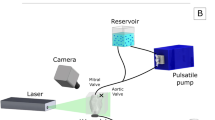

The Isolated Heart

Hearts of 4 landrace pigs (80–106 kg) were explanted according to the protocol described previously.22 Briefly, a median sternotomy was performed in the anesthetized pigs and the aorta was cannulated with a cardioplegic needle. After exsanguinating around 2 L of blood via the iliac artery, the ascending aorta was clamped distally to the cardioplegic needle and 1 L of Custodiol (Dr. Franz Köhler Chemie GmbH, Bensheim, Germany) was slowly applied. Simultaneously, the heart was cooled with a slurry ice solution. The heart was then excised and prepared for the connection to the isolated heart apparatus. All vessels of the right atrium were ligated using 4-0 Prolene sutures. All vessels of the left atrium were also closed except one pulmonary vein that was connected to the preload reservoir. The HVAD (Medtronic plc, Dublin, Ireland) sewing ring was attached to the ventricular apex to facilitate coring and pump implantation with orientation of the LVAD inflow cannula towards the mitral valve.

The isolated heart apparatus featured three connections to the heart: First, the aorta was connected to an air-trapped reservoir mimicking the arterial Windkessel53 system; Second, the pulmonary artery was connected to an open venous reservoir to eject the coronary flow against a low pressure; Third, the left atrium was cannulated and connected to a pressure-controlled air-trapped reservoir which constituted the preload adjustment system (Fig. 1).

For cardiac resuscitation, Langendorff perfusion was used as the pressure in the arterial reservoir was gradually increased until 70 mmHg was reached.22 Thereby, the coronary arteries were perfused with oxygenated blood and the heart was rewarmed to a normothermic temperature of 37 °C. If necessary, the hearts were defibrillated and/or paced to achieve a stable sinus rhythm. Once the heart stabilized, an HVAD was attached and the setup was switched to the working mode, in which the heart pumps blood from the preload reservoir towards the arterial one. By adjusting the preload, afterload, and pump speed, different levels of LVAD support (unsupported, full, and partial support) were achieved. Characteristic pressure (APT300, Harvard Apparatus, Hollisten, MA, USA, see Fig. 1) and flow signals (SONOFLOW CO.55/120, Sonotec, Halle, Germany, see Fig. 1) were recorded with a signal processing and control board (MicroLabBox, dSPACE GmbH, Paderborn, Germany).

A microbubble solution was injected into the preload reservoir, from where it was immediately transported into the left ventricle and visualized in the B-mode images (Fig. 2). The microbubbles were created by forcefully agitating saline and air (5–10 vol% air) between two syringes connected with a three-way stopcock for at least five times 5,16,26,35 until the solution became partly opaque and white. For each heart, B-mode sequences in DICOM format were recorded for an unsupported, partial, and full support condition.